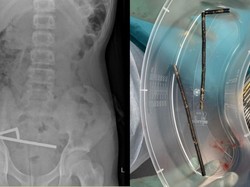

Seorang Remaja Telan Hampir 200 Magnet, Sebagian Usus Hilang

Remaja di Selandia Baru menelan hampir 200 magnet dan belum diketahui alasannya. Operasi dilakukan dan dia harus kehilangan sebagian usus.